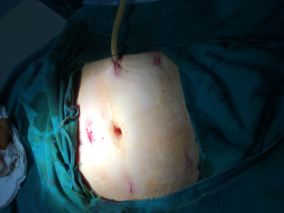

?我院成功開展腹腔鏡下“子宮廣泛切除+盆腔淋巴結(jié)清除術(shù)”?近日,我院成功為一位宮頸癌早期患者實施了腹腔鏡下“子宮廣泛切除+盆腔淋巴結(jié)清除術(shù)”。本次手術(shù)的成功開展,標志著我院婦產(chǎn)科腹腔鏡手術(shù)技術(shù)達到了市級同行的領(lǐng)先水平。?危險:陰道不規(guī)則出血 ?竟是癌魔來襲39歲的患者王女士(化名),2年前曾因“宮頸...